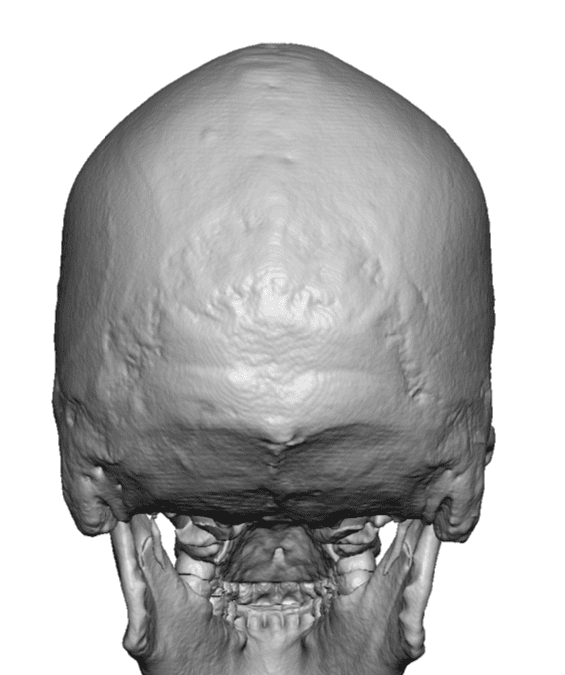

Severe narrowing skull deformity from prior sagittal craniosynostosis repair as an adult.

Complete replacement of entire skull by a custom implant with temporal fat injections.